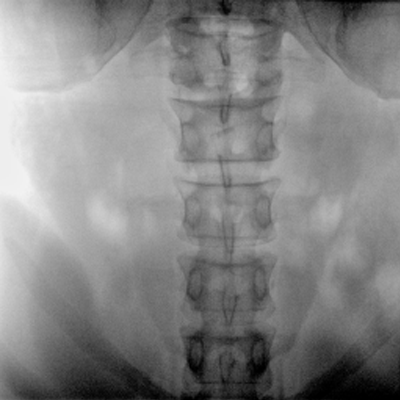

Clinical picture

臨床圖片